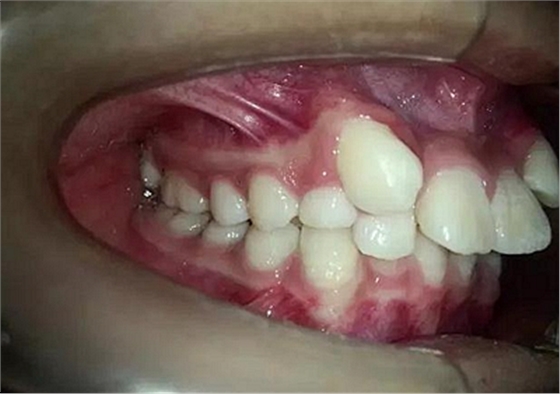

患者13歲,經(jīng)過一段時間的治療前牙反合已經(jīng)正常,只有左上3尖牙埋伏

14歲,牙齒嚴重擁擠,上頜兩個尖牙在側(cè)切牙唇側(cè)